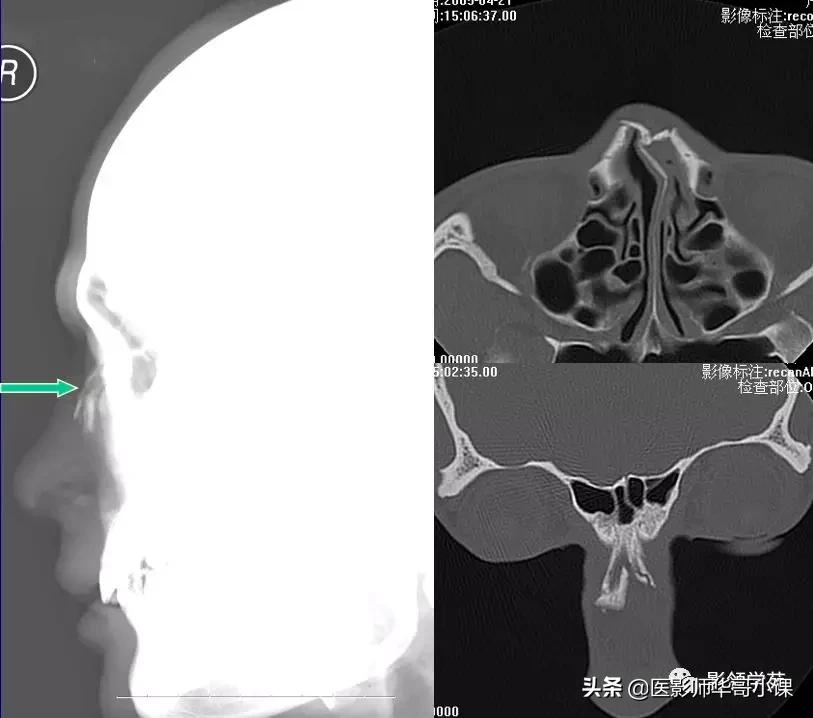

鼻骨正常侧位

鼻骨横断面HRCT

鼻骨冠状面HRCT